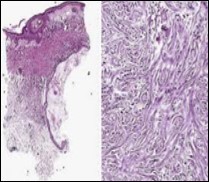

Figure 3.Desmoplastic trichoepithelioma exhibiting accumulated basaloid epithelial cells disseminated amongst a background of abundant fibrous tissue stroma and an attenuated superimposed epidermis 10.

Figure 4.Desmoplastic trichoepithelioma depicting cords and aggregates of basaloid epithelial cells with encompassing dense, compact fibrous tissue stroma 11.

Desmoplastic trichoepithelioma is challenging to discern on clinical and histological grounds, especially when evaluated with miniature, superficial, shave tissue samples. Thus, deep-seated tissue sampling is required. Brownstein and Shapiro in 1977 delineated the morphological features of desmoplastic trichoepithelioma as configuring narrow strands of basaloid tumour cells, keratinous cysts and an encompassing desmoplastic stroma. Aforesaid features exemplify a unique histological triad categorizing desmoplastic trichoepithelioma. Enunciation of a thin walled, attenuated epidermis and an absence of superficial telangiectasia assists the discernment of desmoplastic trichoepithelioma 3, 4.

On gross examination, frequently the tumours are gradually progressive, grey/white or flesh coloured, indurated, non ulcerated with a central depression and a magnitude varying within a few millimetres. The well circumscribed lesion is symmetrical, confined to papillary dermis and upper two thirds of reticular dermis. Emergence of narrow strands of basaloid epithelial cells, numerous horn cysts, a dense, encompassing fibrous tissue stroma, foreign body granulomatous reaction, several foci of calcification and articulation of osteoma within the lesion provide diagnostic characteristics 3, 4.

Nests, strands and miniature cords of basaloid epithelial cells of variable dimension, encompassed within a dense fibrotic tissue stroma are observed within the upper and mid-dermis. Cellular aggregates are rimmed with collagen bundles, multiple horn cysts appear within the stroma and a layering of stratified squamous epithelium is enunciated. Foci of calcification are apparent. Mitotic figures, peripheral palisading, apoptotic bodies aggregated within the epithelium or cellular and nuclear pleomorphism are absent 3, 4

Commonly, miniature strands of basaloid cells are encompassed within a desmoplastic stroma in association with keratinous cysts, usually abutting or attached to basaloid cell aggregates. Superimposed epidermis demonstrates a mild atrophy in accompaniment with enlarged cords of tumour cells aggregated within the mid - dermis. Connective tissue hyperplasia is observed within the horn cysts 4, 5.

Lesions are generally superficial and infrequently invade lower dermis. Tendency for peri-neural or intra-neural infiltration, cogitated in adjunctive cutaneous carcinomas, is exceptional in desmoplastic trichoepithelioma. Nevertheless, desmoplastic trichoepithelioma can be exemplified as a component of particularly desmoplastic, cutaneous carcinomas demonstrating foci of peri-neural involvement 4, 5. Figure 1, Figure 2, Figure 3, Figure 4, Figure 5, Figure 6, Figure 7, Figure 8.